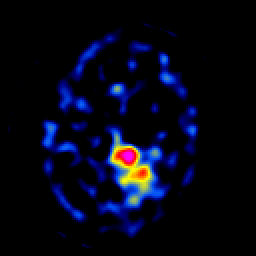

SPECT TL Study #7 -- Slice #39